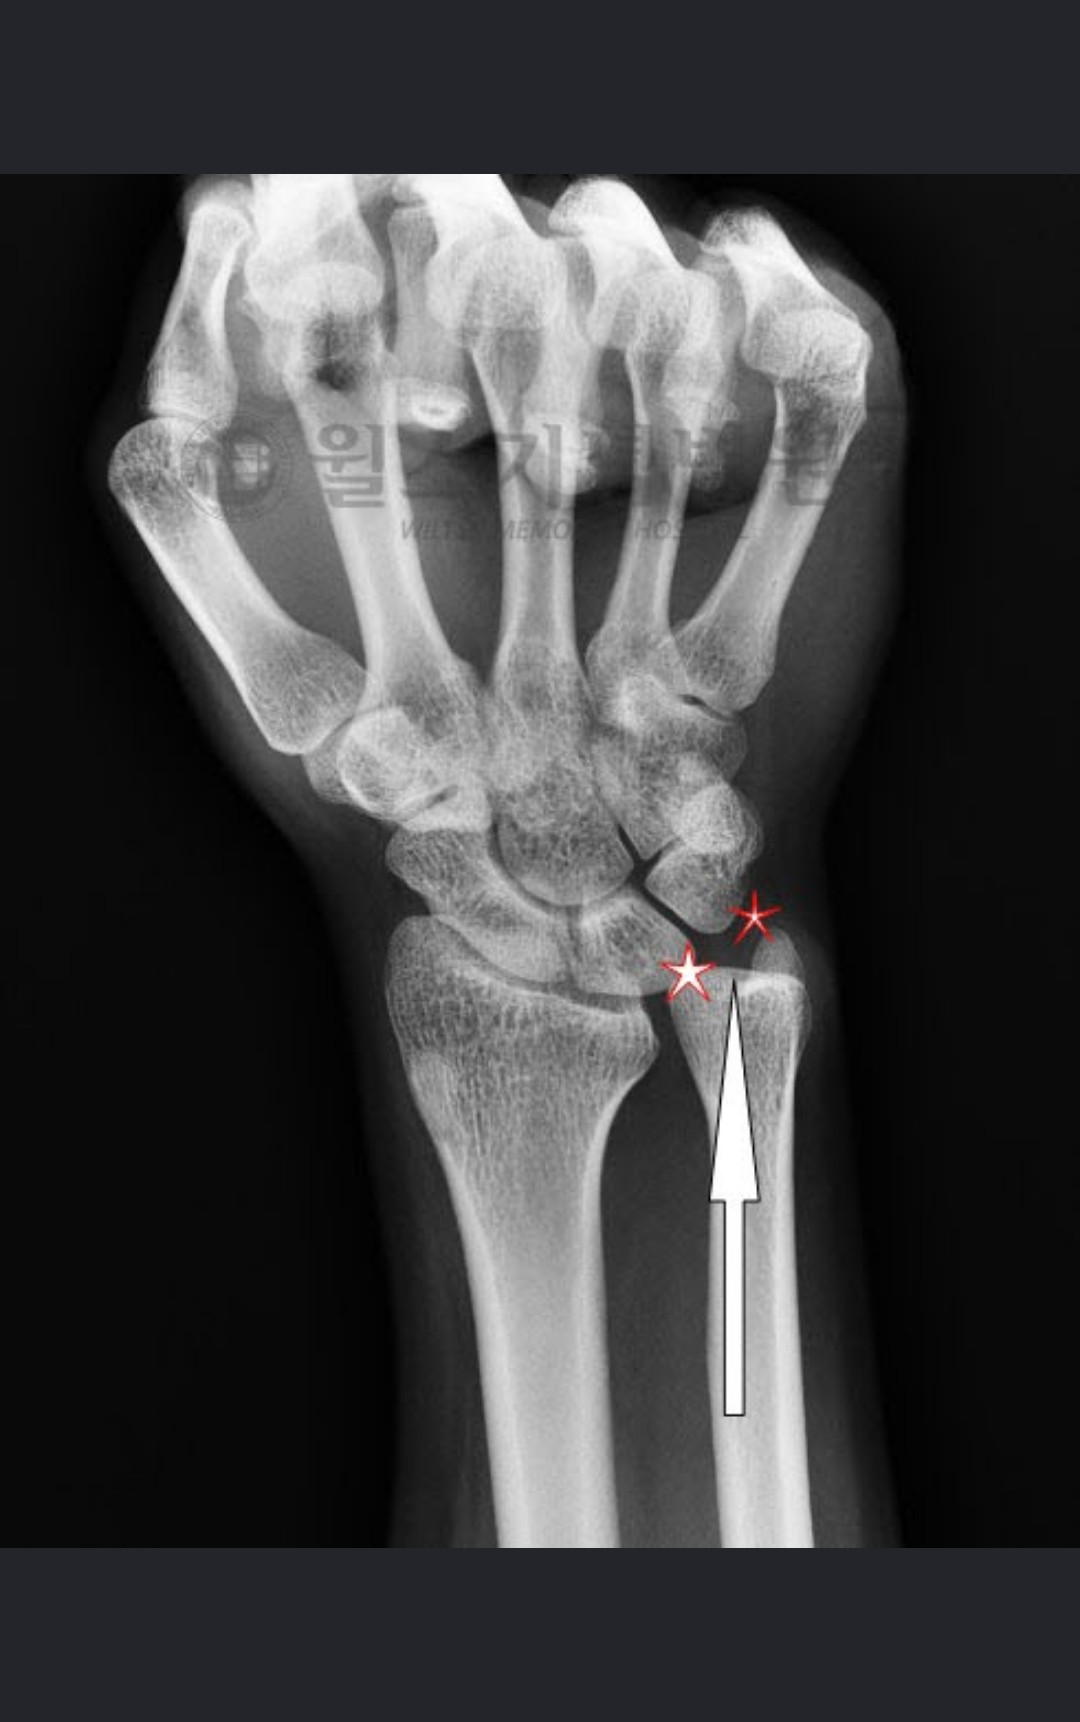

최근 대학병원에 다녀왔다. 손목의 통증 때문이다. 중학교 때부터 통증을 갖고 있다가 최근에 원인을 알게 되었다. 손목의 뼈는 요골과 척골이 있는데 척골이 상대적으로 길다고 한다. 그래서 움직이거나 손목을 비틀 때면 연골이나 인대와 충돌하는 현상이 빚어진다. 부딪히면서 찢어지기도 하고 통증을 유발하게도 된다. 그래서 잘 사용하지 않다 보니 오른손에 비해 왼손의 활용이 서툴고 악력도 많이 떨어져 있다. 근본적인 치료는 수술로 가능하다는 설명에 고민 끝에 수술하기로 결정하고 왔다. 척골을 5mm 정도 잘라서 높이를 맞추는 수술이다. 멀쩡한 뼈를 잘라서 다시 붙여야 한다니 부담스러운 것은 사실이다.

[척골 충돌 증후군]